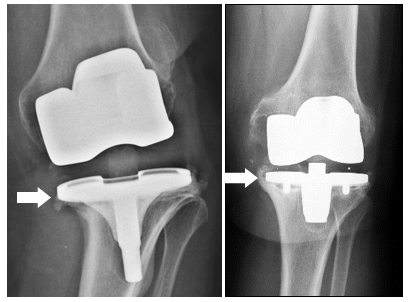

COMMON REASONS for a prosthesis replacement on the knee are, in addition to infection, e.g., instability or persistent pain.

In the context of a repeated knee operation,

special implants are often necessary to replace defective ligaments (using a so-called

coupled prosthesis) or to rebuild bone defects (using augments or bone replacement material).